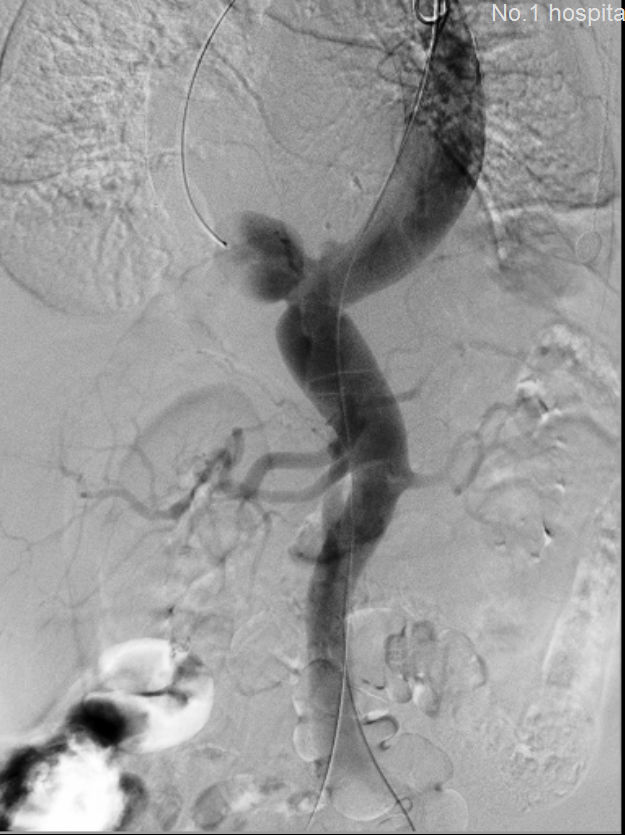

“行了!”,随着最后一枚支架的植入,郭平凡悬着的一个心终于落了下来,

介入手术室里的全体医务人员也都松了口气。造影确认,撤除导丝导管,缝合切口,安全护送病人回到重症室监护,患者生命征平稳,各项指标正常,又一例濒

临破裂的腹主动脉瘤在血管外科、急诊科、影像科、麻醉科、介入手术室等科室医务人员的通力配合下取得了成功。

术前 术后